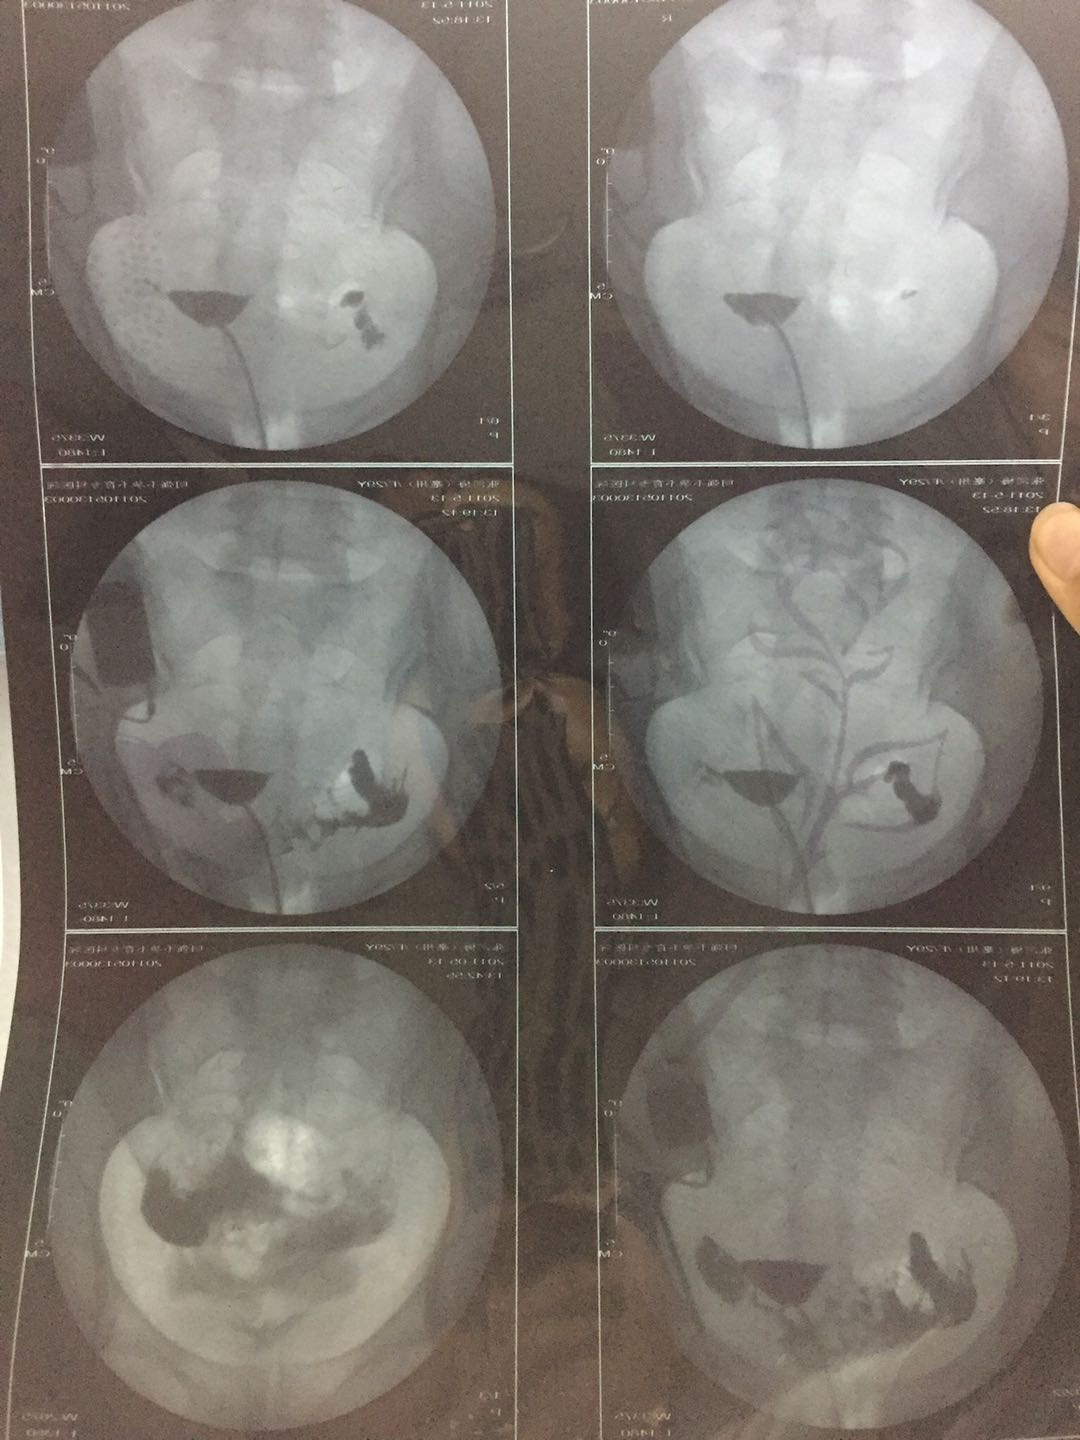

这种必须做手术么还是取了胚胎不是非要做

这个手术不是非得要马上做,需要根据你的年龄、生育计划等来综合评估并权衡利弊后再决定是否需要手术以及什么时候做。如果是做试管通常为了避免输卵管积液及炎症因子逆流至宫腔影响胚胎着床等,会行输卵管结扎等手术,这个手术通常在移植前完成